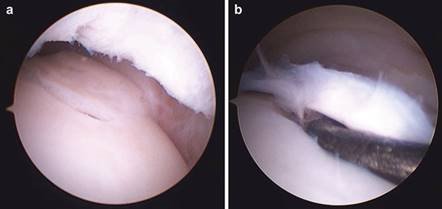

Clinical & Radiographic Imaging Archive

Clinical Image